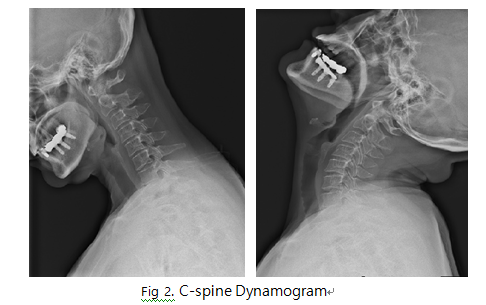

C-Spine Dynamogram

1. 목적

- C-spine의 정상적인 전후 운동과 각 spine간의 불안정성에 의한 추체의 미끄러짐, 추간강의 압축이나 벌어짐, dislocation 등의 병변 유무를 관찰한다.

6) 영상 결과